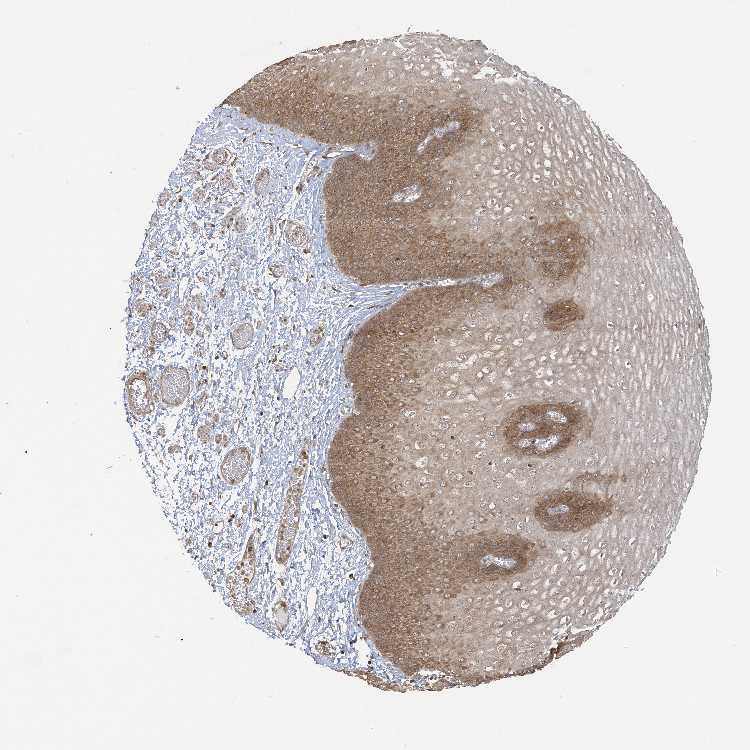

Antibody HPA034621

Squamous epithelial cells Medium